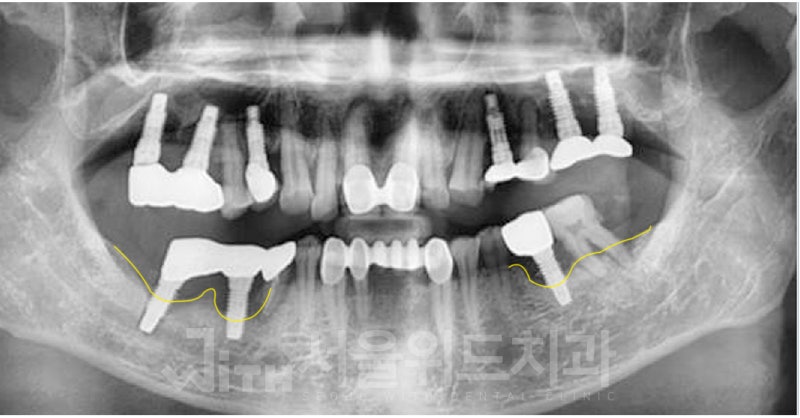

많은 분들이 치아가 상실되는 문제를 겪고 있다 하더라도 원인, 상실된 기간, 구강 환경 등에 따라 다양한 방법의 임플란트가 적용될 수밖에 없다는 사실을 알아야 했습니다. 경험이 부족한 전문의와 함께하면 이러한 니즈를 고려할 수 없게 되고 결국 만족도가 낮아질 수 있기 때문에 고난도 임플란트 시술도 잘하는 전문의와 함께하여 건강한 구강 환경을 오래 유지할 수 있도록 해야 했습니다.게다가 잇몸뼈 상태를 확인하는 것도 중요하다고 생각해야 하는데 총 2회에 걸쳐 잇몸뼈 상태를 확인해야 보다 안정적인 수술을 할 수 있기 때문입니다. 따라서 이러한 과정을 거쳐 길고 안정적으로 사용할 수 있는 임플란트를 완성해야 했습니다.치아가 탈락하지 않고 단순히 손상된 경우에는 전악보철 풀마우스를 고려하는 것이 좋으나 이는 치아를 발치하여 식립하는 것이 아니라 신경치료와 지르코니아 크라운을 통해 전악을 재건하는 것이므로 자연치아 상실을 막으면서 잃어버린 심미성과 기능성을 되찾을 수 있다는 장점이 있었습니다.공석을 대체하는 것은 환자에게 단 한 번의 기회였을지도 모릅니다. 따라서 치과 선택이나 치료 방향을 설정하는 과정에 매우 신중해야 하지만 분당 임플란트를 해야 하는 상황임에도 불구하고 통증과 이차적인 문제에 대한 두려움으로 조치를 미루고 있다면 내비게이션 임플란트를 고려해 보면 좋은 시도가 되었습니다.내비게이션 임플란트는 기존 아날로그 인상 획득과 같은 불편한 과정 없이 임플란트를 완성할 수 있다는 장점을 가지고 있으므로 특히 신체적 기능이 약한 분들은 이러한 방법을 적극 이용해야 함을 알려드립니다.앞서 말했듯이 무절개로 적은 통증만으로 빠르게 시술할 수 있는 것은 사실이지만 무분별한 무절개는 오히려 임플란트를 오래 사용하지 못하게 할 수 있기 때문에 절개 여부는 의료진과 충분히 상의한 후 결정하도록 해야 했습니다.그리고 식립 각도의 오류는 잘못된 임플란트의 대표적인 예라고 할 수 있으므로 식립하기 전에 식립 위치, 깊이, 방향 등을 정밀하게 분석하여 단 0.1mm의 오차 범위도 놓치지 않도록 하는 것이 현명했습니다.이와 함께 개인 치열이나 잇몸 모양에 딱 맞게 제작된 맞춤 임플란트 지대주를 적용하면 후속 문제의 우려를 줄일 수 있으므로 이를 통해 완전한 임플란트를 위한 또 다른 조건을 충족할 수 있어야 했습니다.시간적 여유가 없으신 분들도 평일 야간 또는 주말에 진료하는 장소를 통해 여유롭게 치료받을 수 있었습니다.그리고 미리 예약을 해주시면 더 빨리 진료를 받을 수 있기 때문에 이를 통해 내원의 부담을 덜어드리는 것이 좋았습니다.화목요일에는 오후 9시까지, 주말에는 오후 2시까지 진료하여 환자 편의를 우선시하고 있어 적기에 올바른 진료를 받을 수 있었습니다.접근은 이미지를 통해 간단하지만 상세하게 확인할 수 있음을 알려드리며 이상으로 분당 임플란트에 대해 알아보는 시간을 가졌습니다.연세청춘치과의원 경기도 성남시 분당구 백현로101번길 11 동현프라자 201호연세청춘치과의원 경기도 성남시 분당구 백현로101번길 11 동현프라자 201호연세청춘치과의원 경기도 성남시 분당구 백현로101번길 11 동현프라자 201호